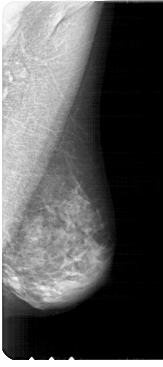

A_1914_1.LEFT_MLO

LEFT_MLO LINES 5326 PIXELS_PER_LINE 2446 BITS_PER_PIXEL 12 RESOLUTION 43.5 OVERLAY